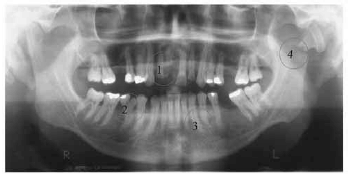

Tendo como referência a imagem radiográfica acima, assinale a opção que apresenta a identificação incorreta.

Com relação aos dentes mostrados na radiografia apresentada no texto, assinale a opção correta.

A partir das informações do texto, julgue os itens que se seguem.

I Pode ser indicado no dente 26 a colocação de núcleo radicular e de uma coroa total estética, se o tratamento endodôntico estiver adequado.

II Houve perda de espaço mesiodistal que precisa ser recuperado antes da colocação da restauração definitiva.

III O material estético mais indicado é o cerômero.

IV Houve perda de estrutura na distal do dente 15, provavelmente por iatrogenia durante preparo cavitário anterior.

A quantidade de itens certos é igual a